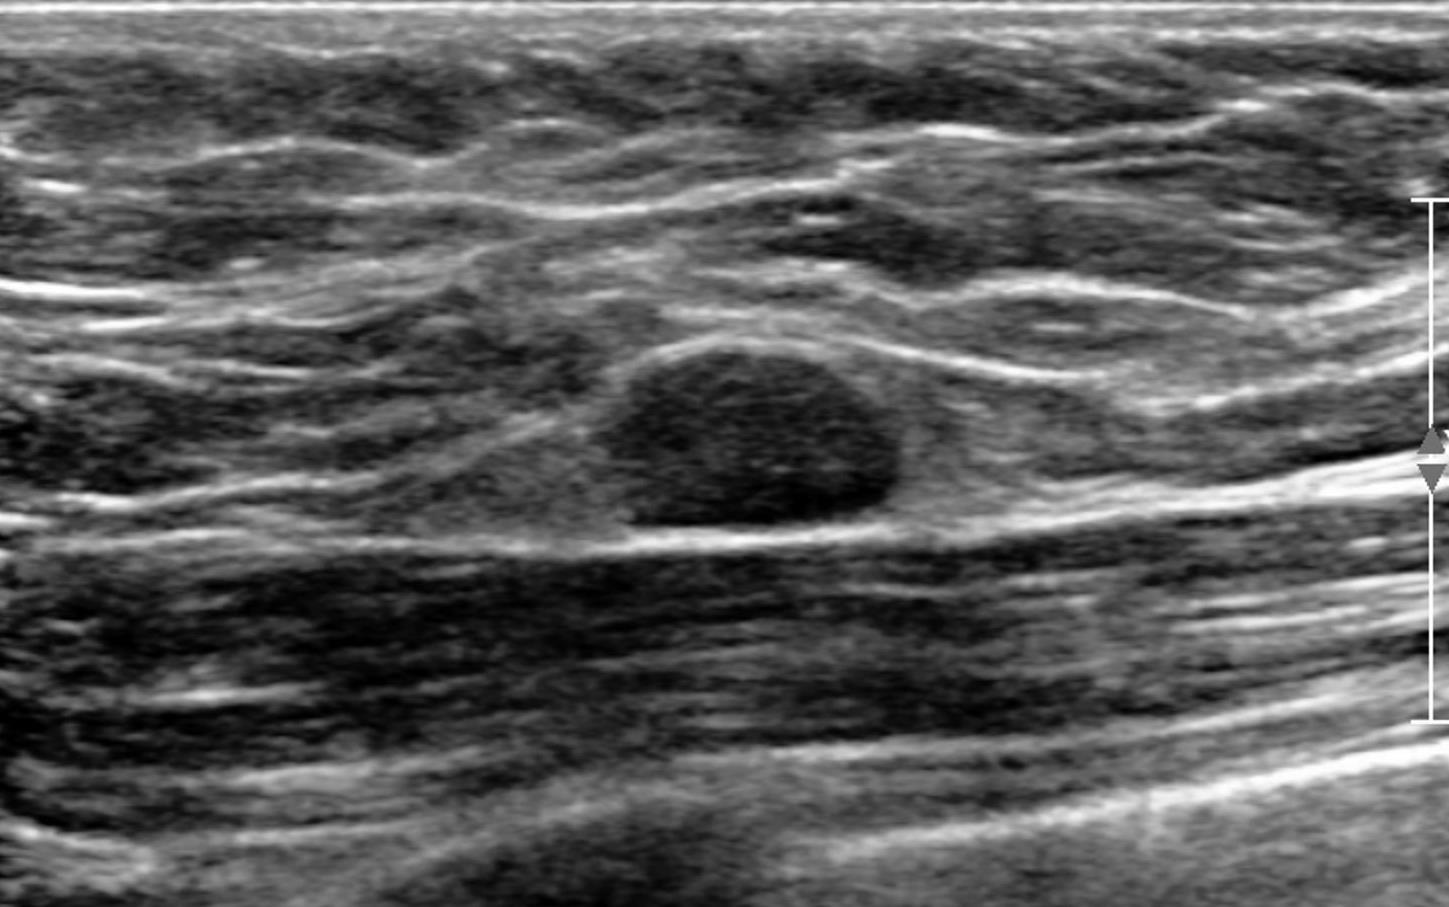

Ultrasound showed at 12 o’clock position in retroareolar region, a complicated cyst with thick nodular wall measuring 4.4x3.1x5.0 cm. Right axilla showed two round LN with effaced hila measuring 0.6 cm.

Ultrasound commonly shows irregular hypoechoic confluent mass with tubular extensions, circumscribed hypoechoic mass, skin thickening and edema with axillary lymphadenopathy having reactive features. Less common features include heterogeneous hypoechoic confluent masses with indistinct, lobulated or angular margins, parenchymal distortion with no discrete masses and heterogeneous parenchyma with edema. The lesions and surroundings show increased vascularity. The findings will be normal in 4-20% of the cases. With advanced disease, fluid collections or abscesses may be present.